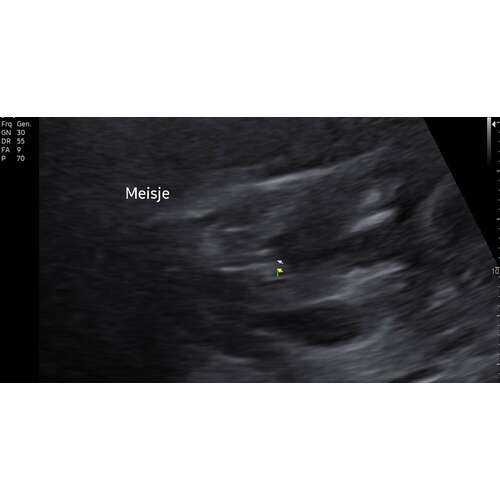

Ik kan mijn originele post niet meer vinden, en staat ook in deel 18 volgens mij, maar wij krijgen een meisje 💓 Ramzi werd meisje gezegd (wel n lastige) en nub werd meisje gezegd. @Nubster, bedankt! 🌹 Ik zal nog even n foto plaatsen van de bevestigde meisjes nub.

Dit is de bevestigde meisjes nub 🥰

Gefeliciteerd!! 💗🎀💞 Dank voor je update ☺️

Ow wat leuk! Toch weer Nubster die t goed heeft!